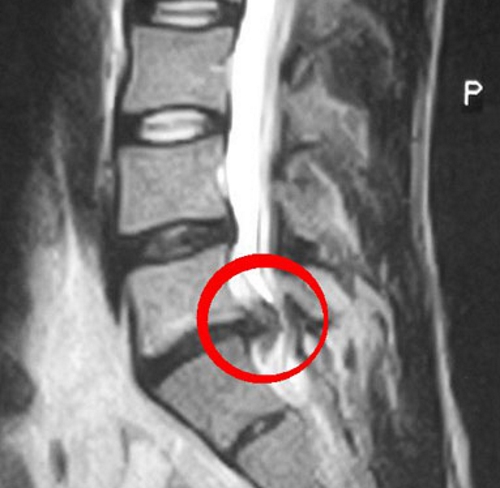

Для более глубокого обследования, направленного на определение степени разрушения тканей и наличия осложнений, применяются:

- УЗИ;

- компьютерная томография;

- МРТ.